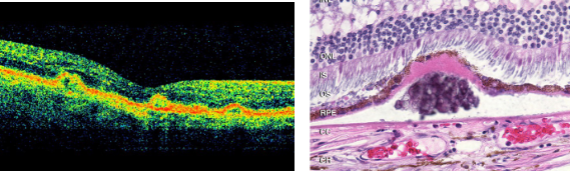

describe type 1 CNVM on OCT

subretinal

describe type 2 CNVM on OCT

retinal angiomatous proliferation

describe type 3 CNVM on OCT

subretinal hyperreflective material

exudation into subretinal space

composed of serum, fibrin, inflammatory cells

may correspond w/ increased risk of GA

serous fluid

type of PED

dome-shaped detachment of RPE

bright diffuse hyperfluorescence that does not spread

fibrovascular tissue

type of PED

irregular RPE w/ speckled fluorescence

hemorrhagic

type of PED

dark elevation of RPE

blocked fluorescence